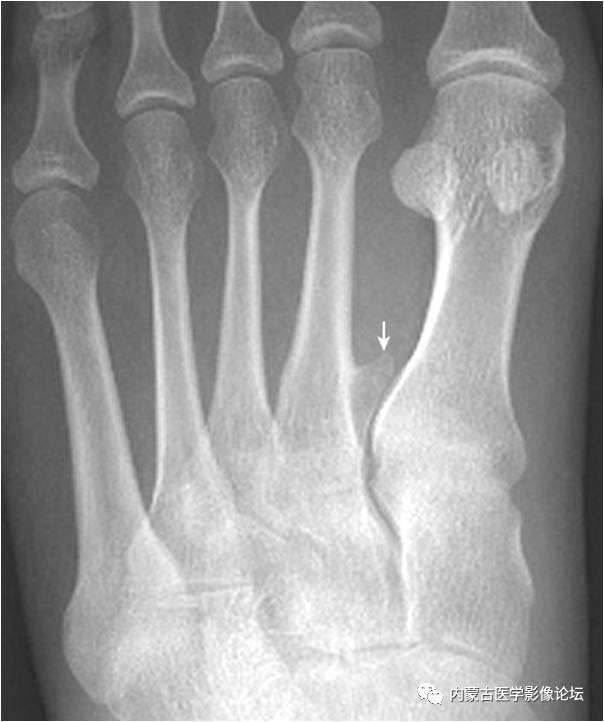

29.跖骨应力性骨折:该例足部疼痛,无外伤史。图示第2跖骨干内侧见斜行透亮线(箭头),邻近伴增厚骨痂(箭),无骨质破坏,提示为疲劳骨折。